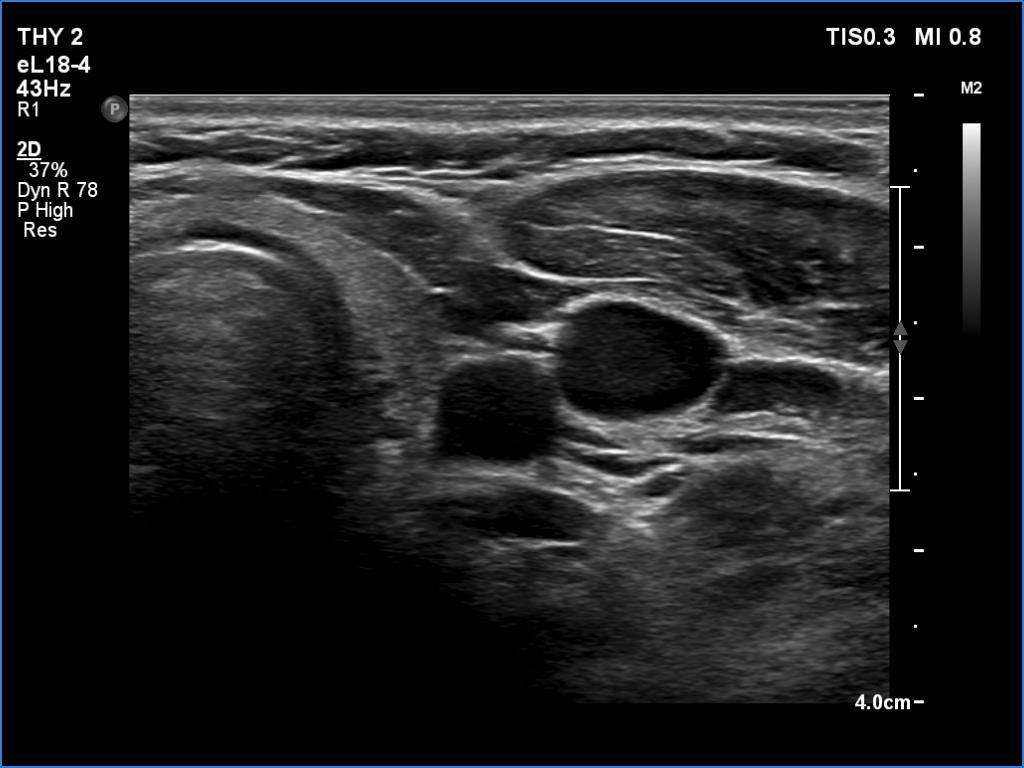

Follow-up examination 6 months later (4th row of images):

Clinical presentation: The complaints of the patient ceased on the day of steroid administration and did not recur. Her thyroid function gradually worsened, it means that the TSH elevated in the past 6 months.

Palpation: no abnormality.

Functional state: subclinical hypothyroidism with TSH 9.61 mIU/L and FT4 10.7 pM/L. CRP and ESR were in the normal range.

Ultrasonography: The thyroid became hypoechogenic and decreased significantly in size while the vascularization was significantly increased.